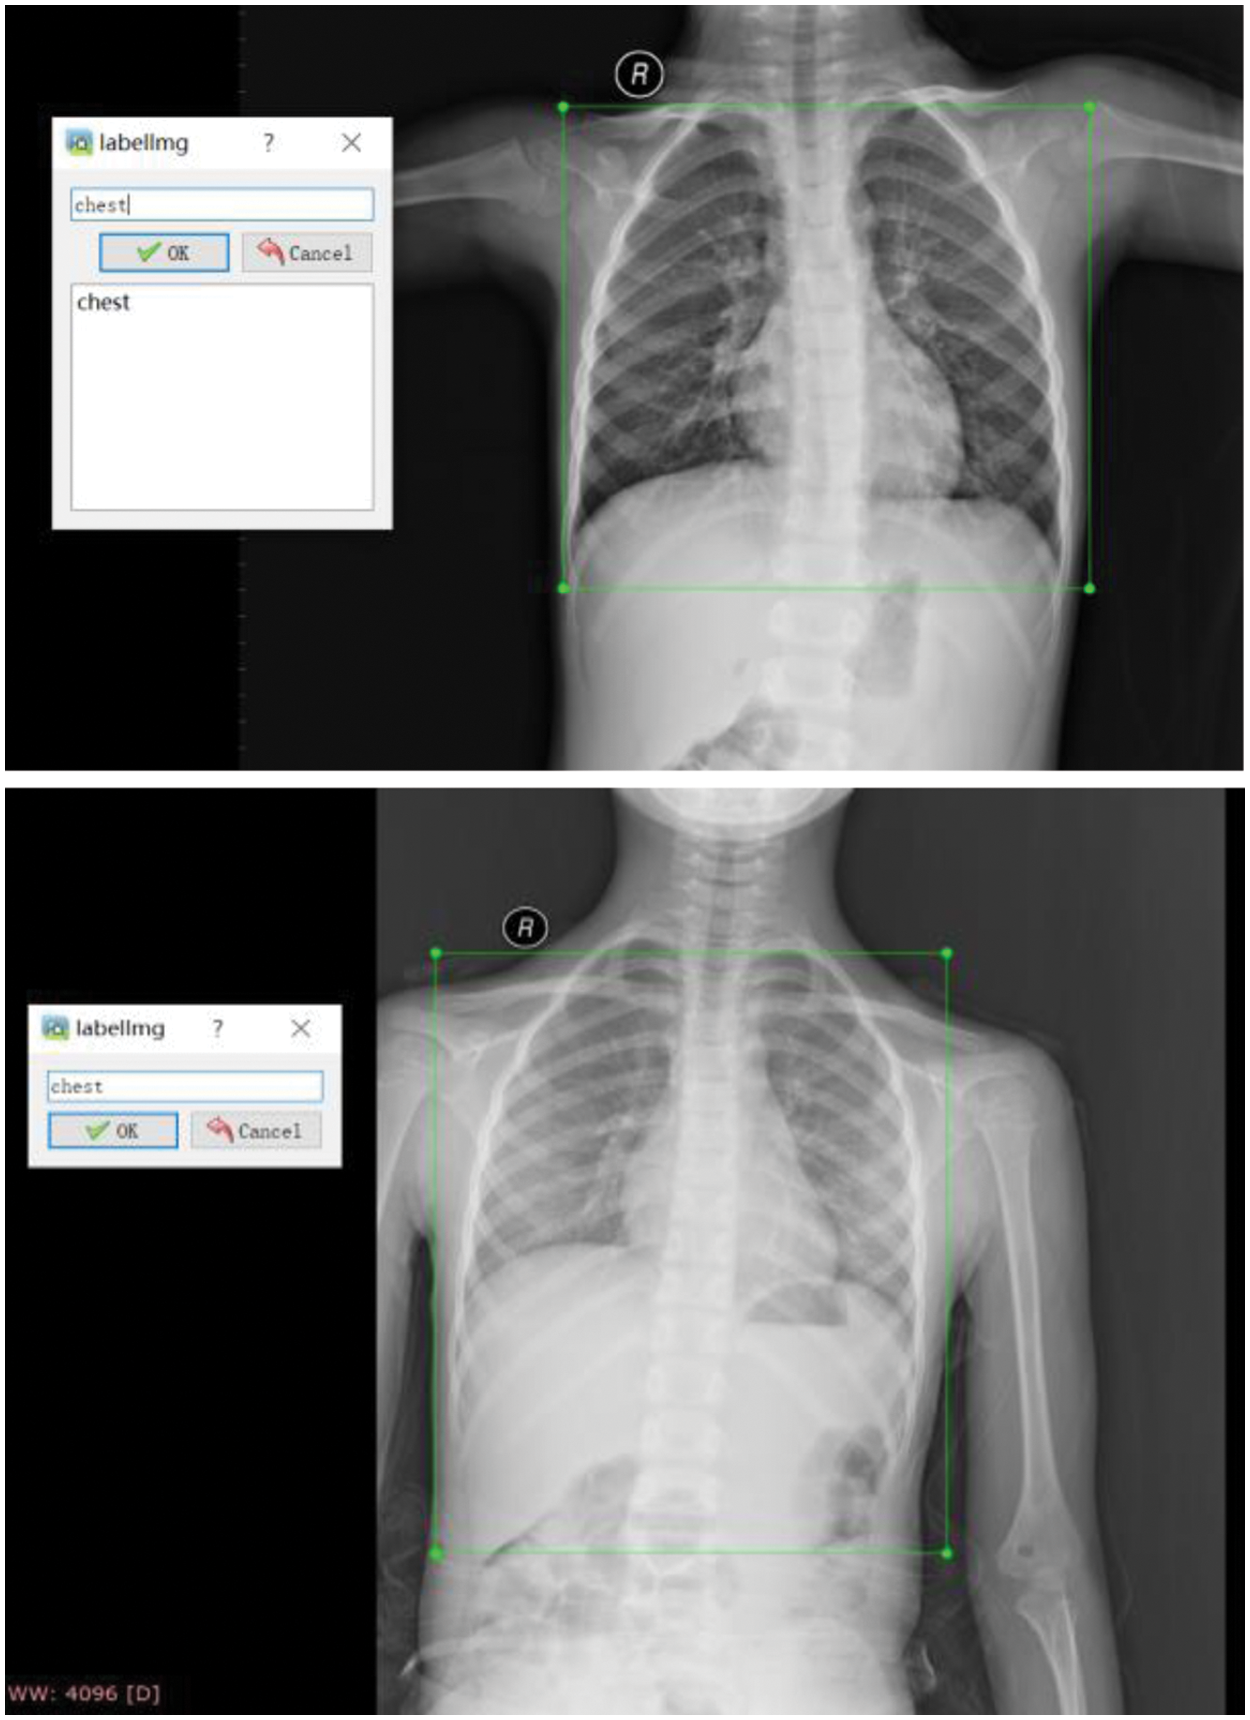

During the training process of YOLOv4, 200 images were first annotated with labeling annotation software, as shown in Fig. 7. These 200 images are used as a training dataset to train YOLOv4. The training mAP for the chest X-ray of the YOLOv4 has reached 100% accuracy. Then, the chest region detection by YOLOv4 would be located and cropped for further FG-CPD. Several cropped images using YOLOv4 are shown in Fig. 8.

Figure 7: Labeling annotated for the raw chest X-ray images